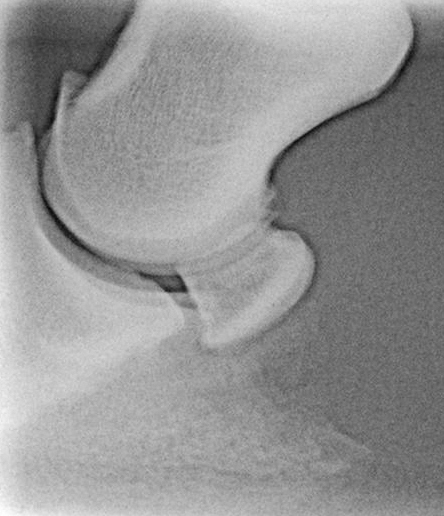

CR5Z18N0J100084_2

Normale seitliche Aufnahme ohne gravierende Veränderungen. Die Gleitfläche des Strahlbeines erscheint rau, was aber auf einer Überlagerung mit dem Hufbeinast beruht.